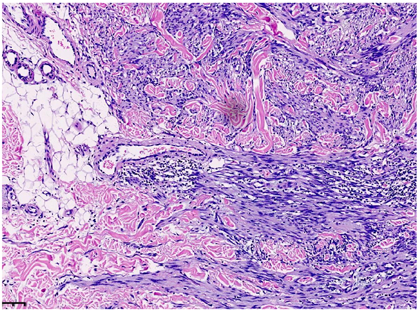

低倍镜下,肿瘤位于真皮层及皮下,肿瘤主要由梭形细胞构成,含有少量卵圆形细胞,部分区细胞丰富,部分区细胞较稀疏,梭形细胞排列成编织状、束状及旋涡状(图1A)。肿瘤细胞与周围组织呈交错浸润性生长,局部呈膨胀性/推挤性生长。肿瘤内薄壁血管较丰富,呈分支状,管腔开放,局部可见少量淋巴细胞浸润(图1B)。肿瘤细胞累及脂肪及皮肤附属器,部分区间质可见黏液水肿/变性及纤维胶原增生(图1C)。

高倍镜下,细胞核呈长/短梭形或卵圆形,染色质细腻/开放,核膜光滑,可见细小核仁。胞浆嗜伊红,较丰富,核浆比尚可。偶见多形性细胞和多核细胞,偶可见核分裂象(热点区约1个/10HPF)(图1D),未见肿瘤性坏死及病理性核分裂。根据FNCLCC分级,肿瘤细胞的形态符合低级别。